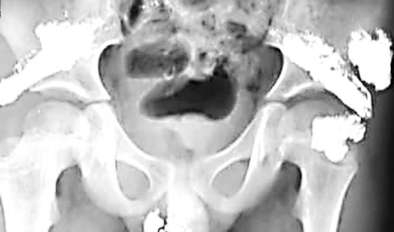

這些“亮晶晶”的東西讓于先生感到很奇怪,為了查明原因,2月5日,于先生帶希希來到昆明醫科大學第一附屬醫院檢查。據X光片檢查結果顯示,希希體內含有大量金屬物質,經醫院診斷,這些金屬是汞,也就是俗稱的水銀。

希希體內存在的水銀,分布在臀部很多位置,且數量驚人。一位護士告訴于先生,希希臀部的水銀量,“最起碼有百八十只溫度計中的水銀含量”。